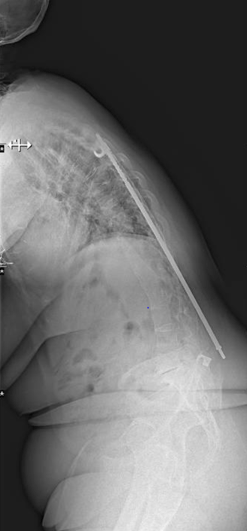

From robotics and AI-driven surgical planning to virtual modeling and custom implants, I’ve embraced a combination of tools that allow me to create tailored surgical plans for my patients—particularly those with scoliosis and spinal deformities.

What sets my approach apart is the seamless integration of these advanced technologies to ensure unparalleled accuracy and better outcomes for each patient.